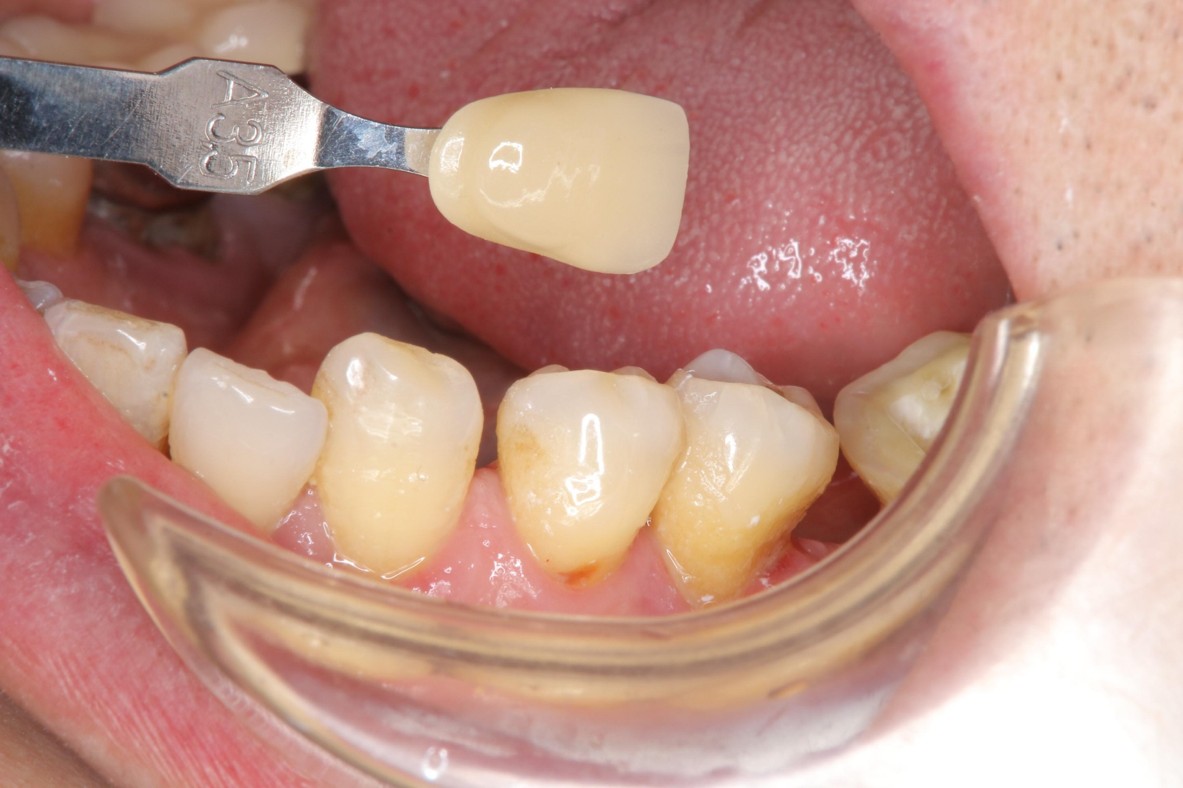

照相比色

上咬合器